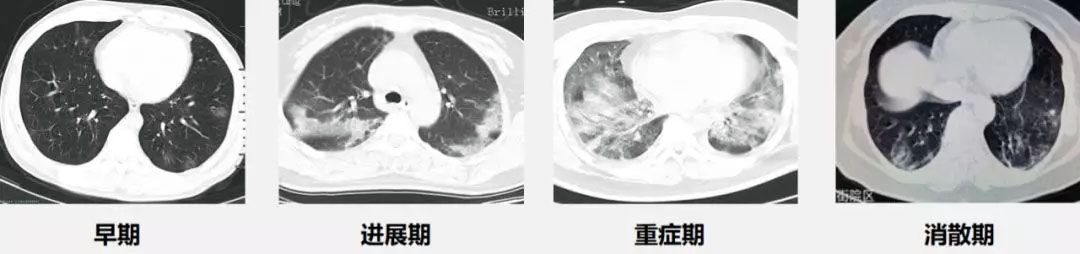

本書通過(guò)影像結(jié)合病理分析新冠肺炎CT早期征象及演變過(guò)程,并列舉大量鑒別診斷病例,圖文并茂,可供放射科醫(yī)師及臨床醫(yī)師參考。通過(guò)識(shí)別新冠肺炎CT早期征象及演變過(guò)程,為臨床提供決策依據(jù),達(dá)到早診斷、早控制、早治療的目的,為有效遏制疫情發(fā)揮應(yīng)有的作用。